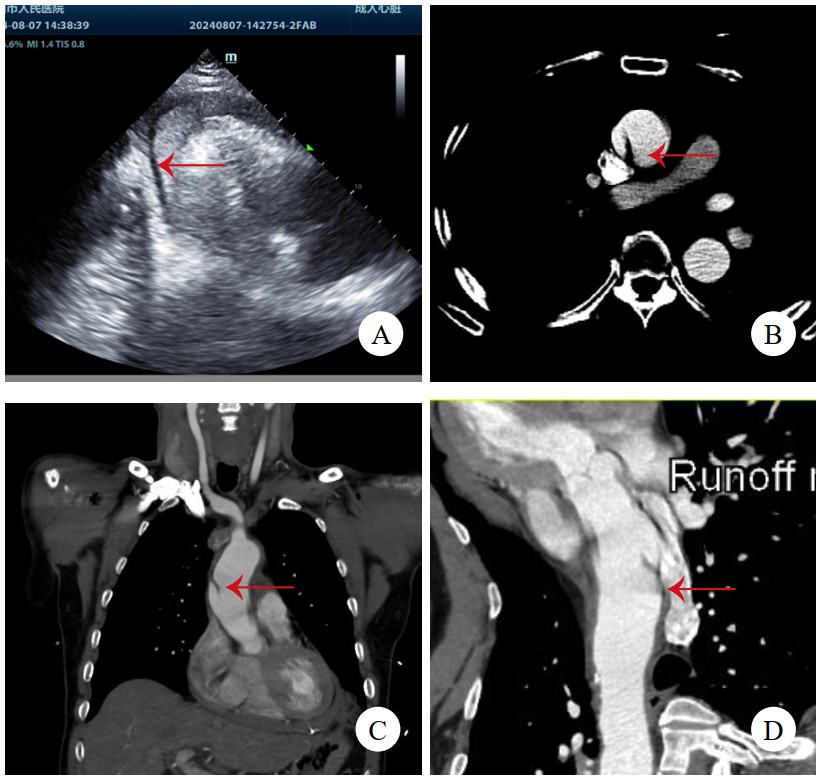

病例3,男,60岁,因“半小时前晕厥1次”就诊。送入抢救室时见患者大汗淋漓,显著呼吸困难,查体:心率97次/min,血压76/52 mmHg(1 mmHg=0.133 kPa),精神极软,颈静脉怒张,心音低钝,未及心脏杂音。立即查床边TTE,见大量心包积液(图 3A)。符合心包填塞,予心包穿刺,见血性液体流出约100 mL后,患者胸闷缓解,心率下降,血压138/88 mmHg。查主动脉CTA,见升弓交界靠上腔静脉侧LIT(图 3B,C,D),该处主动脉直径为31 mm,局部外膜薄层血肿形成。建议手术,患方拒绝,在抢救室留置6 h后生命体征突然消失,后宣布临床死亡。

| 注:A为TTE,箭头示大量心包积液伴血块;B为CTA横断面,箭头示内膜片;C为CTA冠状面,箭头示内膜片;D为CTA多平面重建,箭头示内膜片 图 3 例3患者TTE及CT影像 |